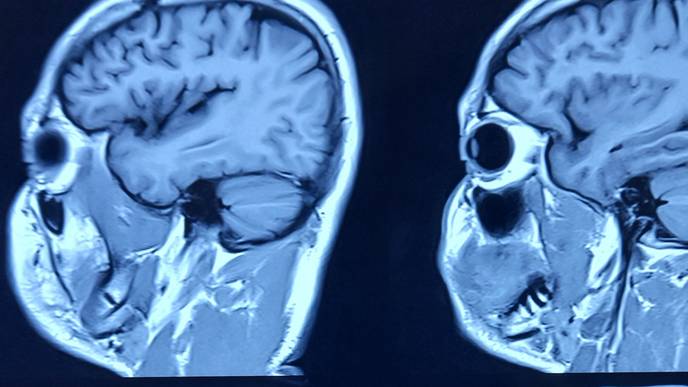

The human brain, a marvel of complexity, operates as an intricate network where various regions collaborate structurally and functionally. These interactions forge complex patterns that underpin the diverse functionalities of the brain. Understanding these complex functions necessitates a deep dive into the brain's networks and the sophisticated interconnections and communication modalities they encompass. Moreover, the exploration of brain network mechanisms opens new vistas in the study of diseases marked by abnormalities in brain function, such as brain injuries and mental disorders, making the investigation of the brain's complex network system paramount for a holistic grasp of its functionalities.

Addressing this challenge, Dr. Chao-Gan Yan and his team from the Magnetic Resonance Imaging Research Center at the Institute of Psychology, Chinese Academy of Sciences, have innovated beyond their previously acclaimed brain imaging processing platform (DPARSF/DPABI/DPABISurf, cited in over 5,000 research works, with the DPABI software paper being distinguished as one of the top 0.01% highly cited papers by ESI and featured among the hot papers in the Chinese medical field for 2015-2019). They unveiled DPABINet, a pioneering platform that amalgamates cutting-edge image processing modules like Brain Connectivity Toolbox, FSLNets, BrainNet Viewer, Circos, SPM, PALM, among others, leveraging docker technology to furnish a user-friendly, cross-platform interface and algorithms. DPABINet's intuitive graphical interface (GUI) empowers users to seamlessly construct brain networks, conduct graph theory analysis, and perform statistical analysis and result visualization with a single click, eliminating the need for programming or scripting expertise. Additionally, DPABINet enhances the research on brain structural networks derived from diffusion-weighted imaging, providing a robust analysis framework for brain structural fiber networks predicated on DPABIFiber's preprocessing results.